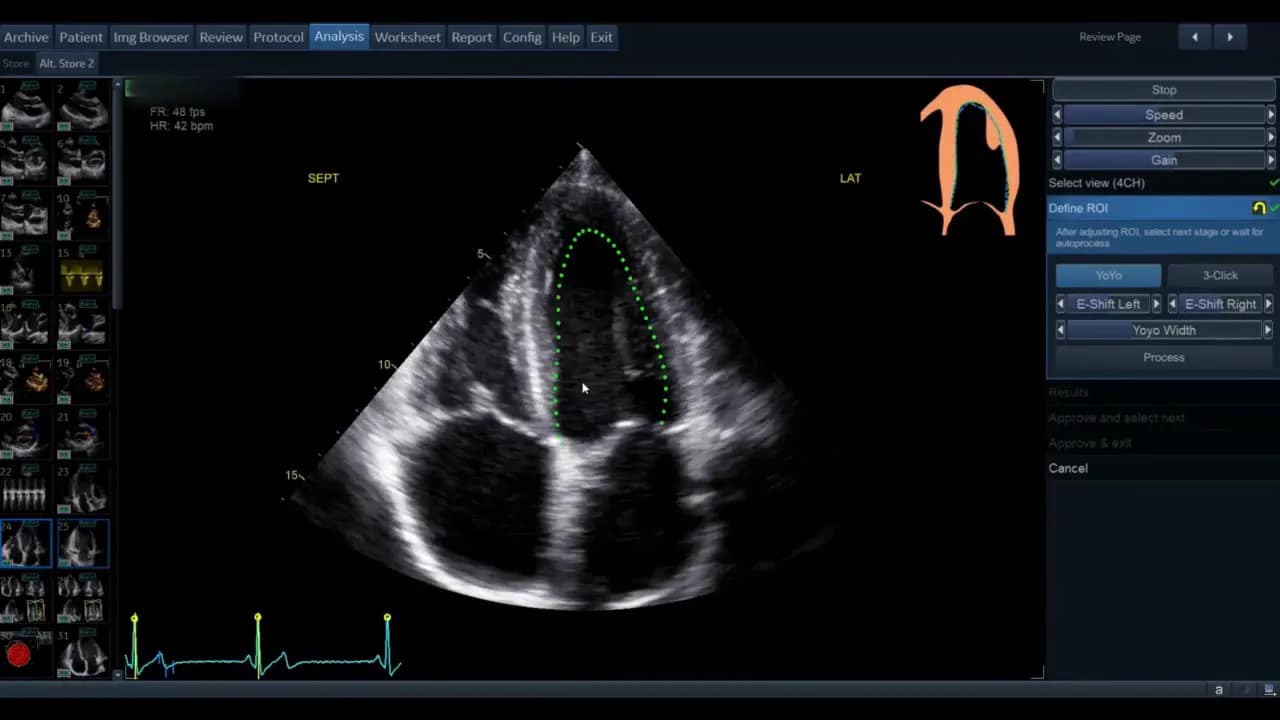

Schritt 3: Region of Interest (ROI) definieren

Sobald die Ansicht gewählt ist, gelangen Sie in die Phase der ROI‑Definition. Hier legt die Software die initiale Kontur für die automatische Wandsegmentverfolgung fest.

Die Standardkontur wird als grüne Linie (modellabhängig) angezeigt. Bewegen Sie den Cursor über diese Linie; rote Kreise erscheinen als Griffpunkte, die Sie anklicken, verschieben und loslassen können. Ziel ist eine möglichst genaue Platzierung entlang des inneren Myokardrandes ohne Papillarmuskeln und Trabekel zu ignorieren, soweit die Software dies zulässt.

- Wenn die vorgegebene Kontur passend ist, genügt das geringe Feintuning.

- Wenn die Kontur unbrauchbar erscheint, nutzen Sie die Drei‑Punkt‑Option. Dabei markieren Sie basal‑septal, basal‑lateral und den Apex manuell. Die Software interpoliert zwischen den Punkten.

Nach der manuellen Markierung können Sie die so erzeugte grüne Kontur wiederum per Griffpunkte feinjustieren. Ziel ist, dass die Kontur den endokardialen Rand im gesamten Zyklus plausibel abdeckt.